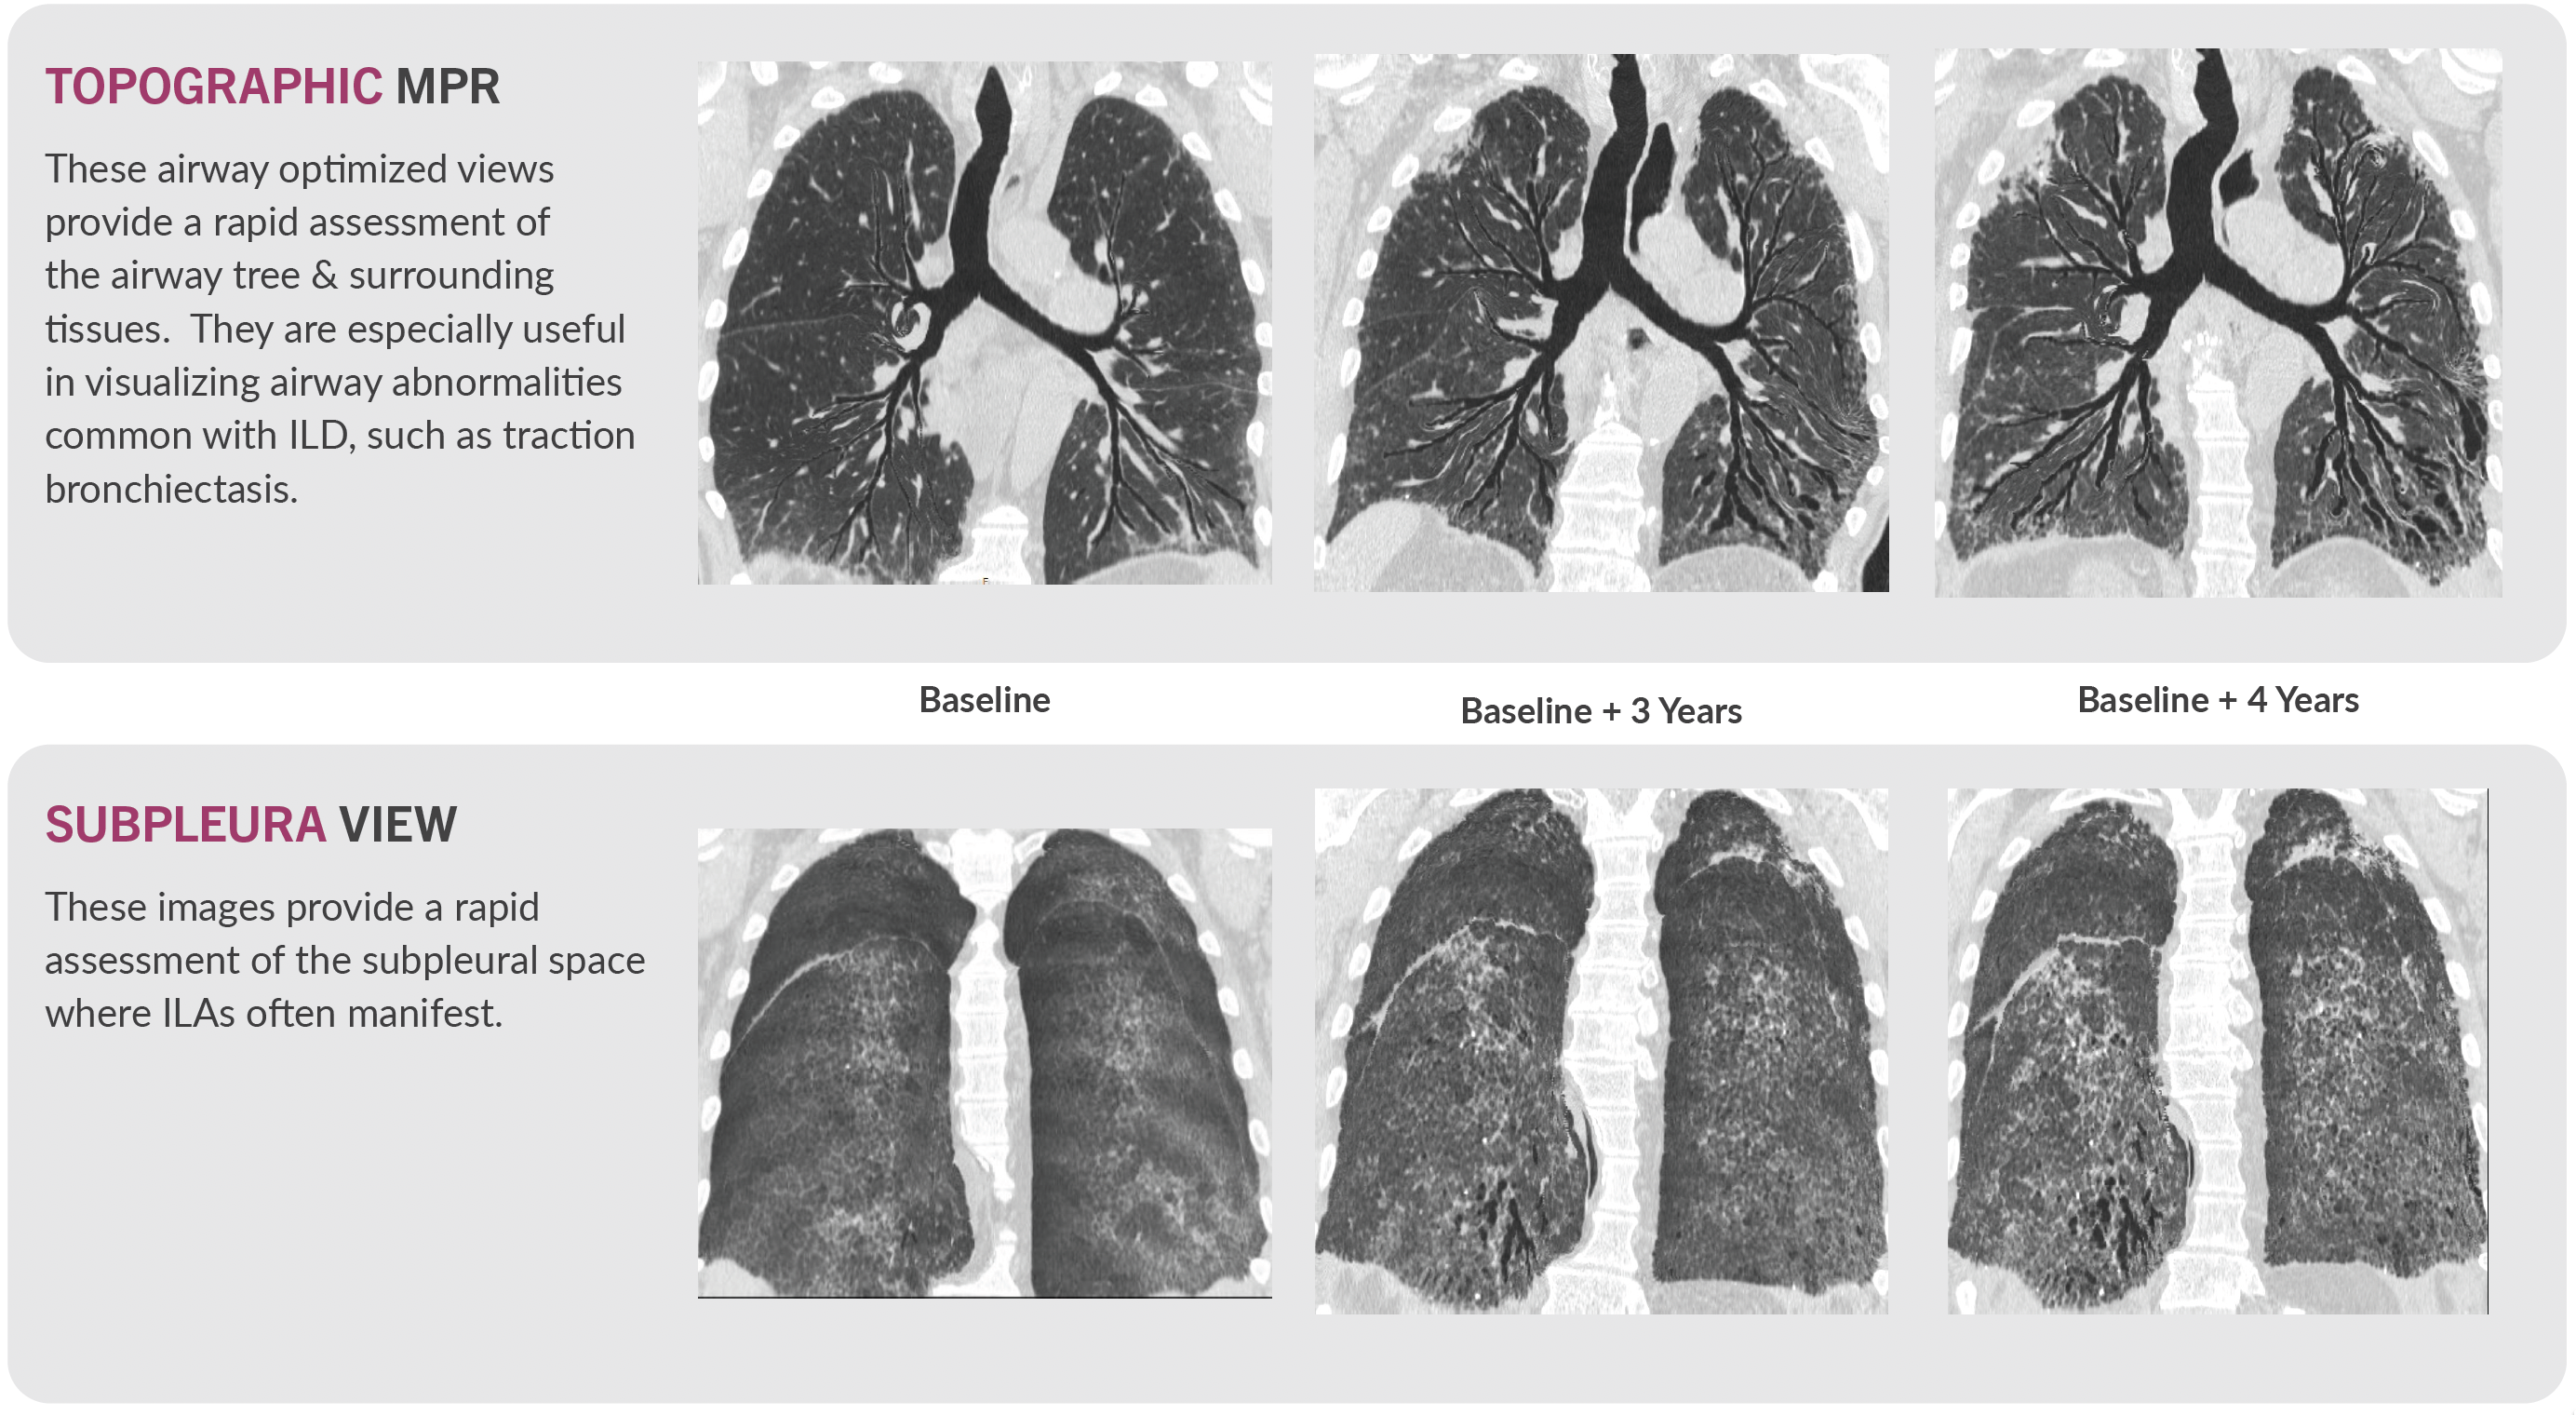

VIDA’s proprietary visualizations complement quantitative measures, providing compelling visual evidence of anatomical changes and therapeutic response. Topographic Multi-Planar Reformat (tMPR) and Subpleura View are two examples.